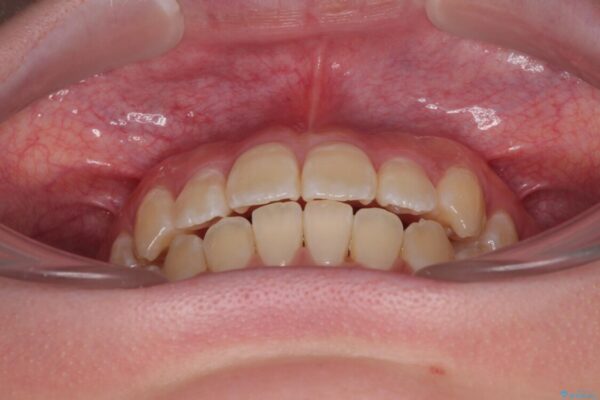

治療後

• 【モニター】前歯のデコボコをスッキリ解消!目立ちにくいワイヤー矯正でスピーディに治療完了 治療後画像

患者様の協力もあり、およそ1年間で治療を完了。スムーズな歯の移動を実現しました。

上下の正中(真ん中のライン)もずれることなく、バランスの取れた美しい歯並びに。笑顔に自信を持てる仕上がりとなりました。

「もっと時間がかかると思っていましたが、あっという間でした。装置も思ったより気にならず、前歯がきれいに並んでとても満足しています。」とうれしいお言葉をいただきました。